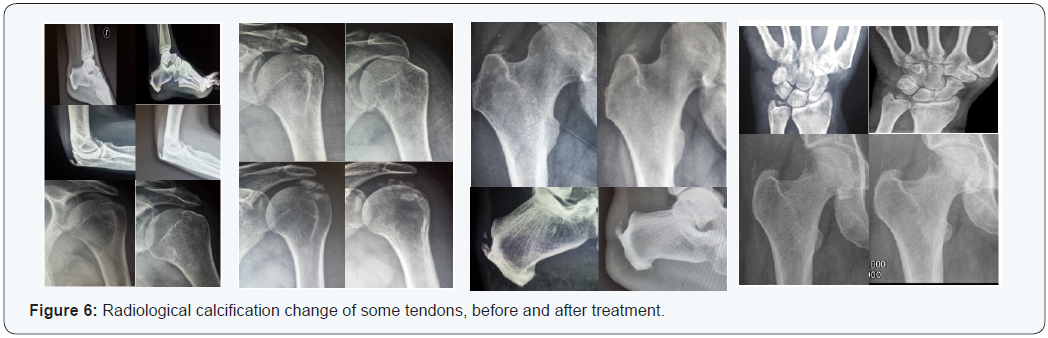

CT is a common, painful, disabling disease, which produces great socio economic impact [16], great demand and high use of resources [17] and labor absenteeism [8], being pain the leading cause of disability due to loss of mobility [8]. In this study, 9.8% of patients (n = 9) had limited mobility. Some authors argue that pain could remain in 50% of cases up to a year after onset [14], while others claim that CT could evolve spontaneously toward healing between 3 and 10 year [18]; this fact worsens patients’ quality of life in their personal, family and work aspects [8]. CT is common in middle-aged working patients (between 30- 50 years) [7,8,16], as it was in the present trial (55 years). CT is more common in women [8,16,19-21], including our study (n=64, 70%). The presences of CT on other articulations different from the shoulder are rare. Only a few case reports make note of these infrequent presentation (CT at the hip and at Achilles tendon). To date, there are neither reports on prevalence nor clinical outcomes on CT of the wrist, elbow or patella (Figure 6).